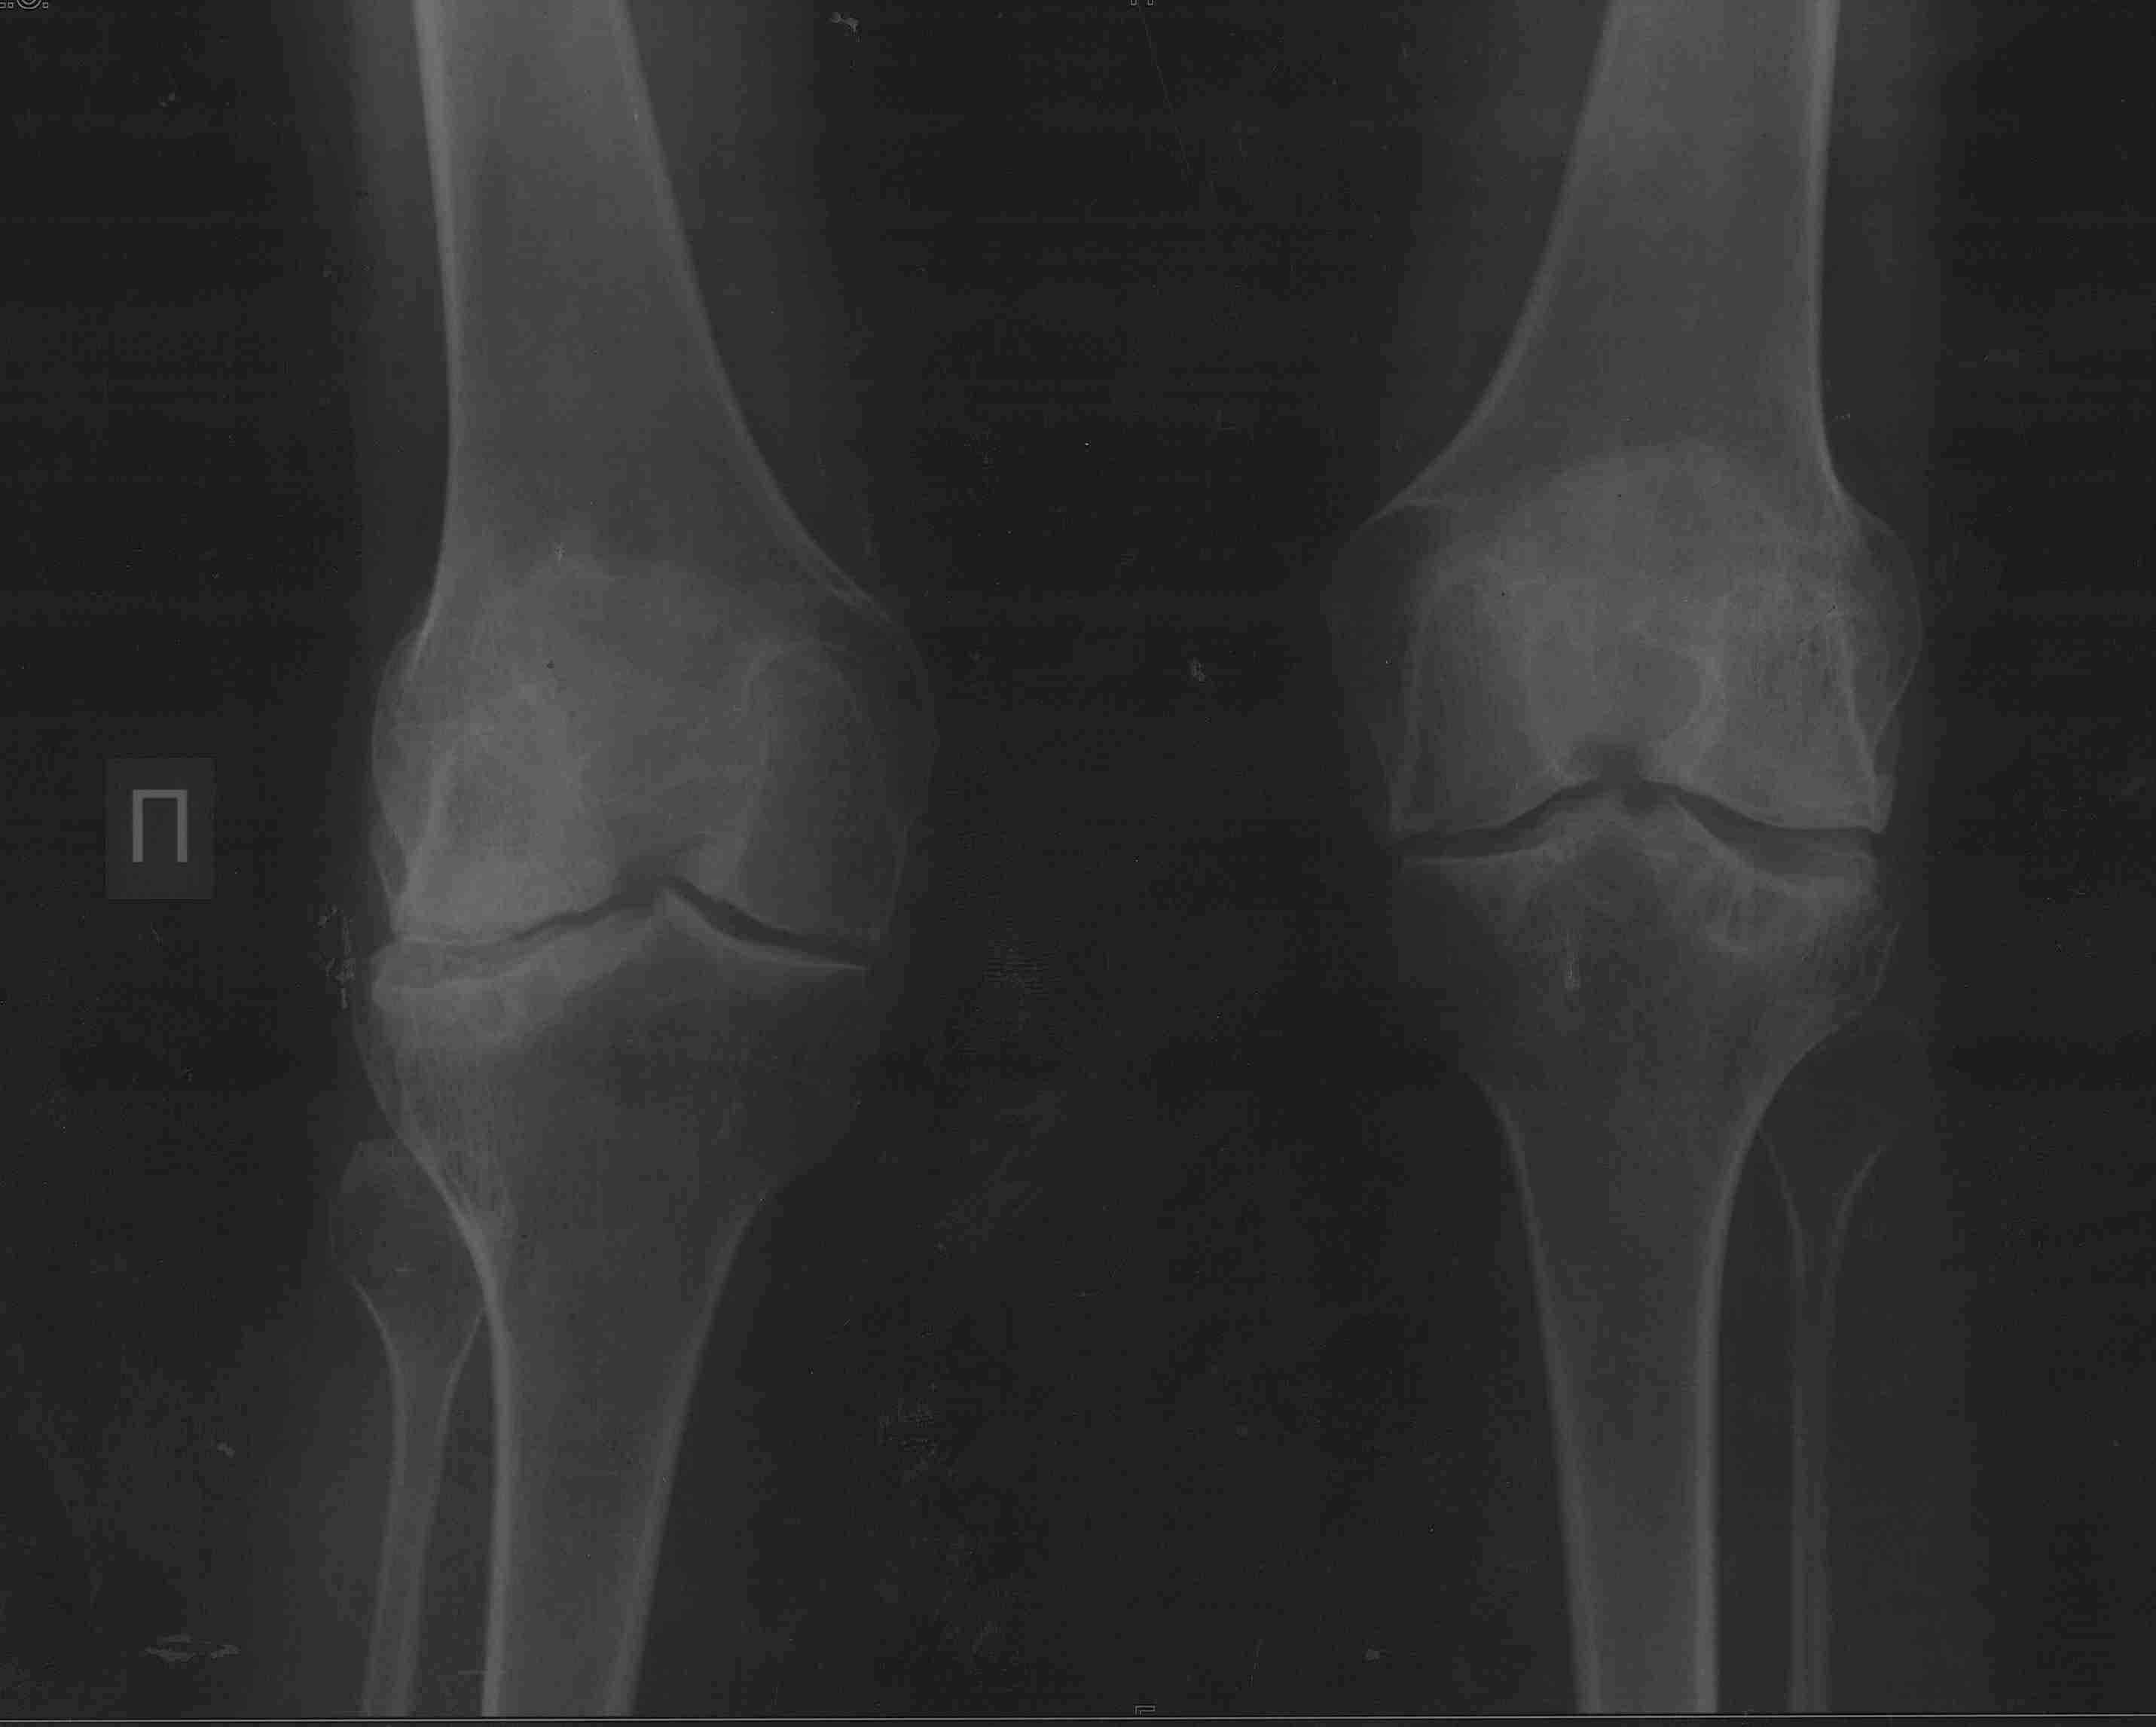

девушка 29 лет с ревматоидным артритом, социальная, лечение получает. вальгусную деформацию на уровне коленных суставов замечает около 10 лет, прогрессирует. Движения в правом коленном суставе:разгибание полное, сгибание около 95-100 град. Боли особой нет. Консультировалась в нескольких НИИ, рекомендовали эндопротезирование.У меня есть желание (вполне, возможно, что и глупое) за сустав "побороться", учитывая возраст, да и первичное протезирование будет не слишком простым. Может исправить деформацию, а там куда кривая судьбы заведет? больше беспокоит боль в голеностопе. В связи с этим есть несколько вопросов: 1. имеет смысл с этим заморачиваться? 2. если да, то в каком объеме? 3. может имеет смысл сделать коррекцию ниже метафиза с одномоментной фиксацией "приличным"гвоздем? Схема прилагается 4. насколько стоит опасаться тракционной нейропатии, стоит сделать острое укорочение или тянуть аппаратом? 5 . еще ряд вопросов, которые я не учел PS книгa Dror Paley пока утеряна вместе с жестким диском, потому не судите строго за дилетанство и приветствуются ваши схемы. Всем большое спасибо за понимание.

Сделаете остеотомию большеберцовой - стопа, которая уже приспособилась к нынешнему положению, повернется кнутри и может утратить контакт с опорой. Голеностопный сустав с признаками выраженной артропатии, скорее всего тугоподвижный. Приспособиться к новому положению не сможет. Значит нужно сразу продумывать последовательность действий, включающую надлодыжечную остеотомию голени или артродез голеностопного сустава (Вам проще оценить его функцию, только по снимку не скажешь). Тем более Вы пишете, что больше беспокоит голеностопный сустав. В этом случае, особенно если думать о надлодыжечной остеотомии, гвоздь может не подойти. А для остеотомий есть хорошие пластины и отработанные техники. С другой стороны, подобное вмешательство можно разбить и на два этапа. Потому что рассчитать все сразу очень сложно. Например, сначала сделать проксимальную остеотомию. Посмотреть, где оказалась стопа и после этого выровнять ее. Но и в этом случае фиксация гвоздем не лучшее решение. Если только не ухитритесь все сделать на одном гвозде. В следующий раз пришлю снимки похожего случая, который делал в 2 этапа.

Максим. Если бы мы вдруг захотели это делать, то остеотомия была бы высокая (над бугристостью). Малоберцовка остаётся интактной. Правда на гвозде не закрепить, но есть пластины

Какую бы не выбрали остеотомию. Выводить ось в ноль я бы не стал. Ориентиром может быть наклон щели голнностопа.

Коленный сустав в итоге надо будет протезировать. За что Вы там собрались бороться? Заболевание воспалительное и захватывает весь сустав, а не только его латеральный отдел. Очевидна варусная установка стопы, что можно попробовать устранить клиновидной остеотомией таранной кости и, возможно, артродезом